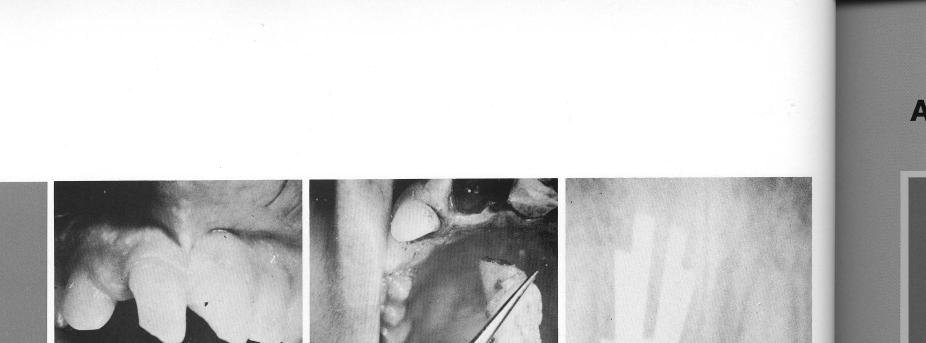

Large diastemas and esthetics (1) suggested a two-unit restoration for the incisors. The abnormal, loose right incisor was extracted (2), and a single-tooth bladevent inserted deep beyond the shallow socket (3). The restoration is a simple, attractive solution (4,5).

2 Maxillary tooth bladevent implant inserted deep beyond shallow socket